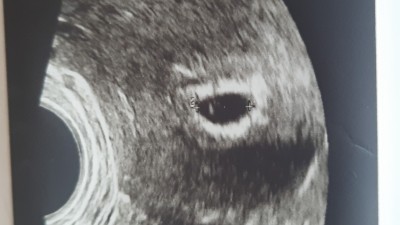

5+6 da gittim dr bilgi vermedi alttan ultarasyonla bakti

image

sadece ultarasyonda gördüğüm kese vardi 10 gün sonra gel dedi ctesi gidecem inşallah bu sefer kalp atışını duyarim